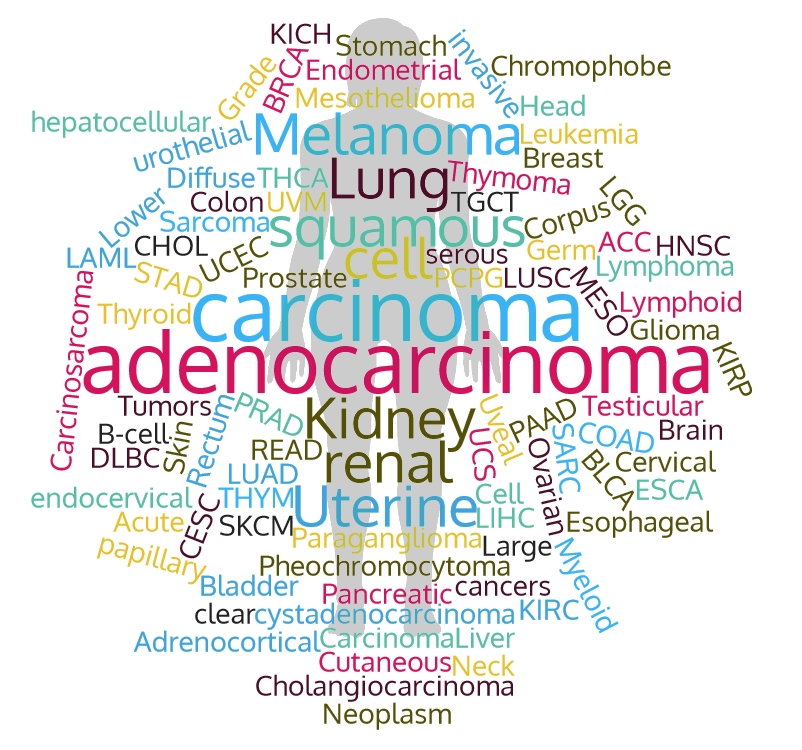

Number of diseases

32

AmiCa is an atlas of miRNA-gene expression in cancer.

We performed an integrative analysis of miRNA-target gene interactions (MTI) on high-throughput molecular profiling of cancer samples obtained from The Cancer Genome Atlas (TCGA). Our study results in correlated MTIs. Our analysis provides a catalogue of MTIs that can serve as a starting point in testing more targeted hypotheses and dealing with cancer functional experiments.

Diseases

To see miRNA and gene expression and their correlations in more detail in samples of a specific disease, select the disease name.

Bladder urothelial carcinoma (BLCA)

Bladder urothelial carcinoma (BLCA) Breast invasive carcinoma (BRCA)

Breast invasive carcinoma (BRCA) Cervical and endocervical cancers (CESC)

Cervical and endocervical cancers (CESC) Cholangiocarcinoma (CHOL)

Cholangiocarcinoma (CHOL) Colon adenocarcinoma (COAD)

Colon adenocarcinoma (COAD) Esophageal carcinoma (ESCA)

Esophageal carcinoma (ESCA) Head and Neck squamous cell carcinoma (HNSC)

Head and Neck squamous cell carcinoma (HNSC) Kidney Chromophobe (KICH)

Kidney Chromophobe (KICH) Kidney renal clear cell carcinoma (KIRC)

Kidney renal clear cell carcinoma (KIRC) Kidney renal papillary cell carcinoma (KIRP)

Kidney renal papillary cell carcinoma (KIRP) Brain Lower Grade Glioma (LGG)

Brain Lower Grade Glioma (LGG) Liver hepatocellular carcinoma (LIHC)

Liver hepatocellular carcinoma (LIHC) Lung adenocarcinoma (LUAD)

Lung adenocarcinoma (LUAD) Lung squamous cell carcinoma (LUSC)

Lung squamous cell carcinoma (LUSC) Mesothelioma (MESO)

Mesothelioma (MESO) Pancreatic adenocarcinoma (PAAD)

Pancreatic adenocarcinoma (PAAD) Pheochromocytoma and Paraganglioma (PCPG)

Pheochromocytoma and Paraganglioma (PCPG) Prostate adenocarcinoma (PRAD)

Prostate adenocarcinoma (PRAD)Citation